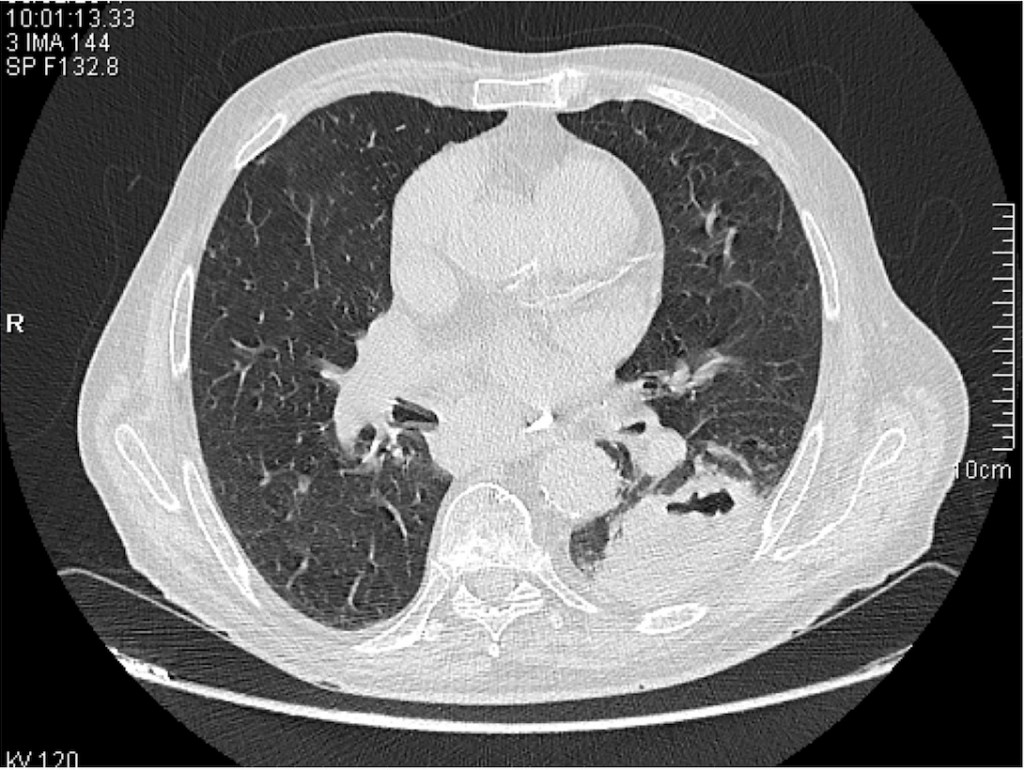

De acuerdo con la lectura sistemática de la placa de tórax, una vez comprobado que los pulmones están igualmente ventilados y perfundidos pasaremos a evaluar sí los hilios son simétricos y la altura de estos, de acuerdo a la anatomía, en que el izquierdo se sitúa ligeramente más craneal que el derecho